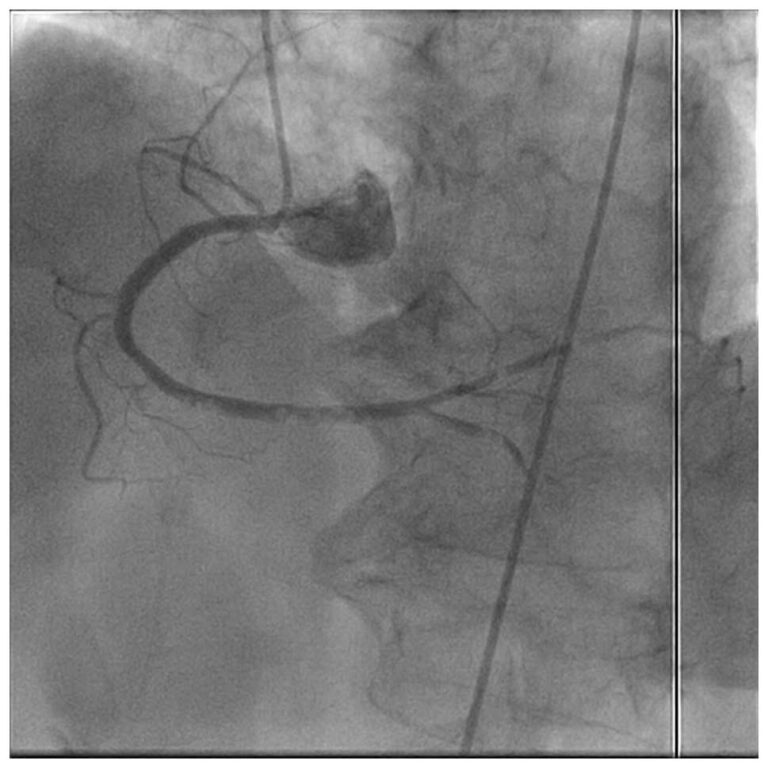

Acute coronary syndrome (ACS) is a clinical presentation ranging from those for ST-segment elevation myocardial infarction (STEMI) to presentations found in non–ST-segment elevation myocardial infarction (NSTEMI) or in unstable angina. It is almost always associated with rupture of an atherosclerotic…